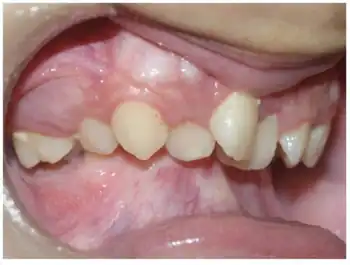

Melnick–Needles syndrome (MNS), also known as Melnick–Needles osteodysplasty, is an extremely rare congenital disorder that affects primarily bone development. Patients with Melnick–Needles syndrome have typical faces (exophthalmos, full cheeks, micrognathia and malalignment of teeth), flaring of the metaphyses of long bones, s-like curvature of bones of legs, irregular constrictions in the ribs, and sclerosis of base of skull.[1]

Melnick-Needles syndrome causes distinctive craniofacial abnormalities. These include full cheeks, a prominent forehead, severe micrognathia and retrognathia. The later two features can cause patients to have difficulty eating and speaking. Other complications that can arise from micrognathia include obstructive sleep apnea, upper airway restriction, increased susceptibility to pneumonia and occasionally even respiratory failure[5]